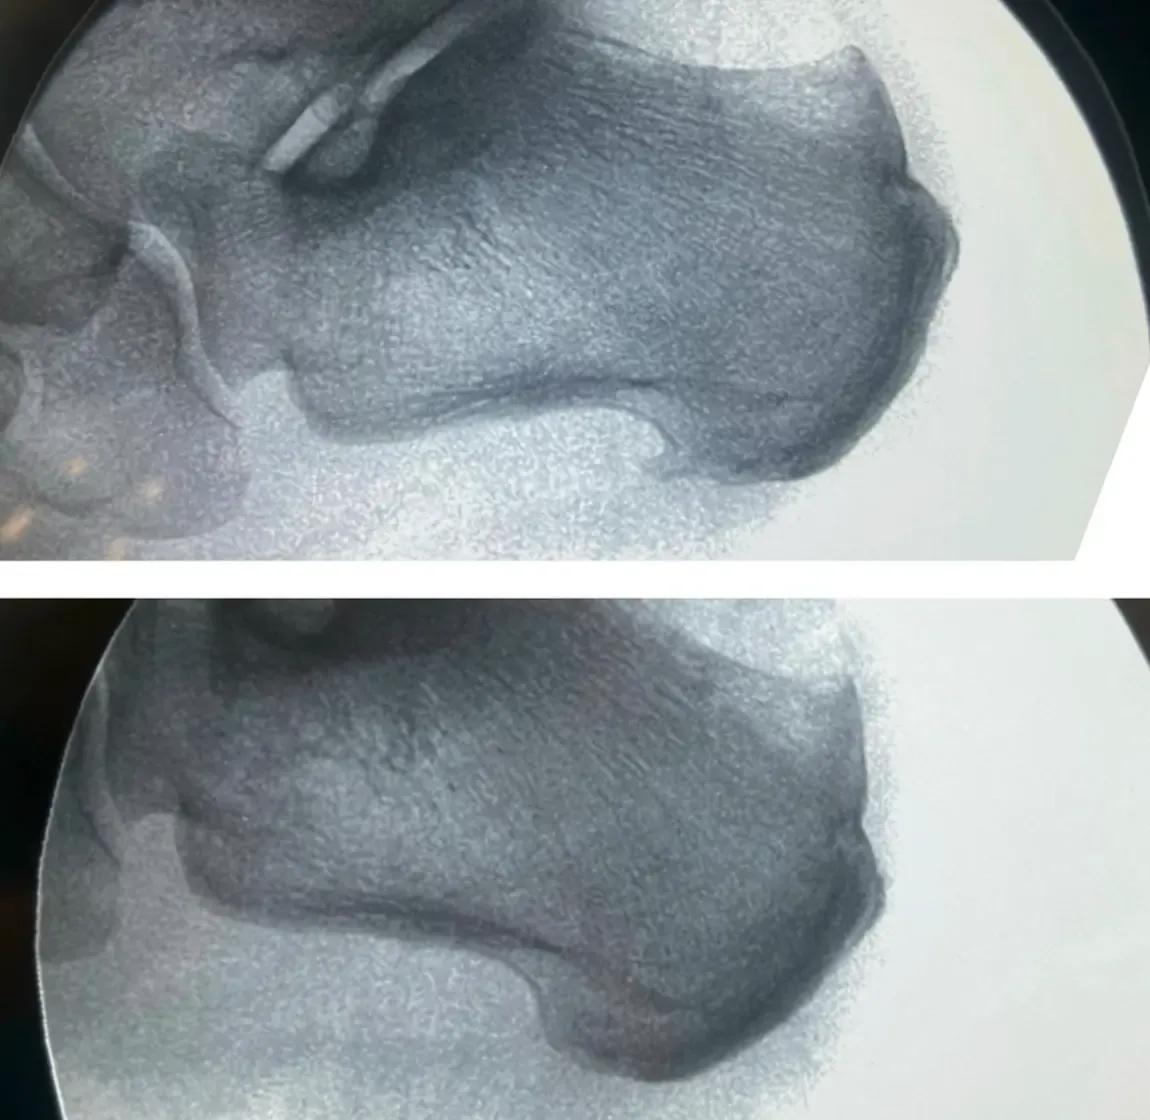

¿“Tienes un espolón” y por eso te duele el talón?

El espolón calcáneo es una calcificación ósea que se forma en la zona donde la fascia plantar se inserta en el hueso del talón (calcáneo). No es una enfermedad ni, en la mayoría de los casos, la causa real del dolor de talón: ese dolor suele venir de la fascitis (o fasciosis) plantar, la inflamación y degeneración de la fascia. Por eso el tratamiento se centra en la fascia, no en el espolón.

¿Qué es Realmente un Espolón Calcáneo?

Un espolón calcáneo es simplemente una calcificación ósea normal que se forma en la inserción de la fascia plantar en el hueso calcáneo. Contrario a la creencia popular, no es una patología sino una adaptación natural del hueso ante las tensiones repetitivas.

Datos que Cambiarán tu Perspectiva:

- 50% de la población tiene espolón calcáneo sin dolor

- El 85% de personas con dolor de talón NO tienen espolón

- La presencia en radiografía NO predice dolor

- Eliminar el espolón quirúrgicamente NO elimina el dolor

Diagnóstico Avanzado: Más Allá de la Radiografía

La Limitación de las Pruebas Tradicionales

¿Te han hecho solo una radiografía para diagnosticar tu dolor de talón? Las radiografías únicamente muestran estructuras óseas, pero el dolor proviene de tejidos blandos que no son visibles en este tipo de imagen.